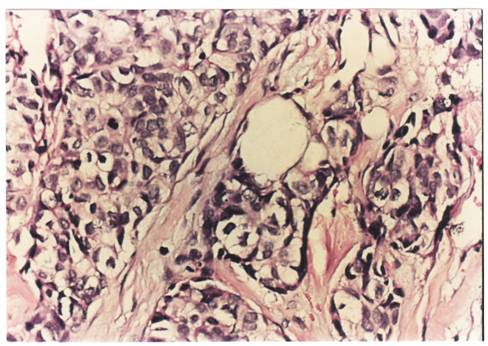

Criterii microscopice de diagnosticare a cancerului mamar

Pentru examenul histopatologic piesele de mamectomie sunt prelucrate prin imparafinare si colorate cu Hematoxilina-Eozina sau, pentru observarea mai buna a tesutului conjunctiv, cu Van Gieson.

Pe preparate colorate, la microscopul optic se observa urmatoarele imagini :